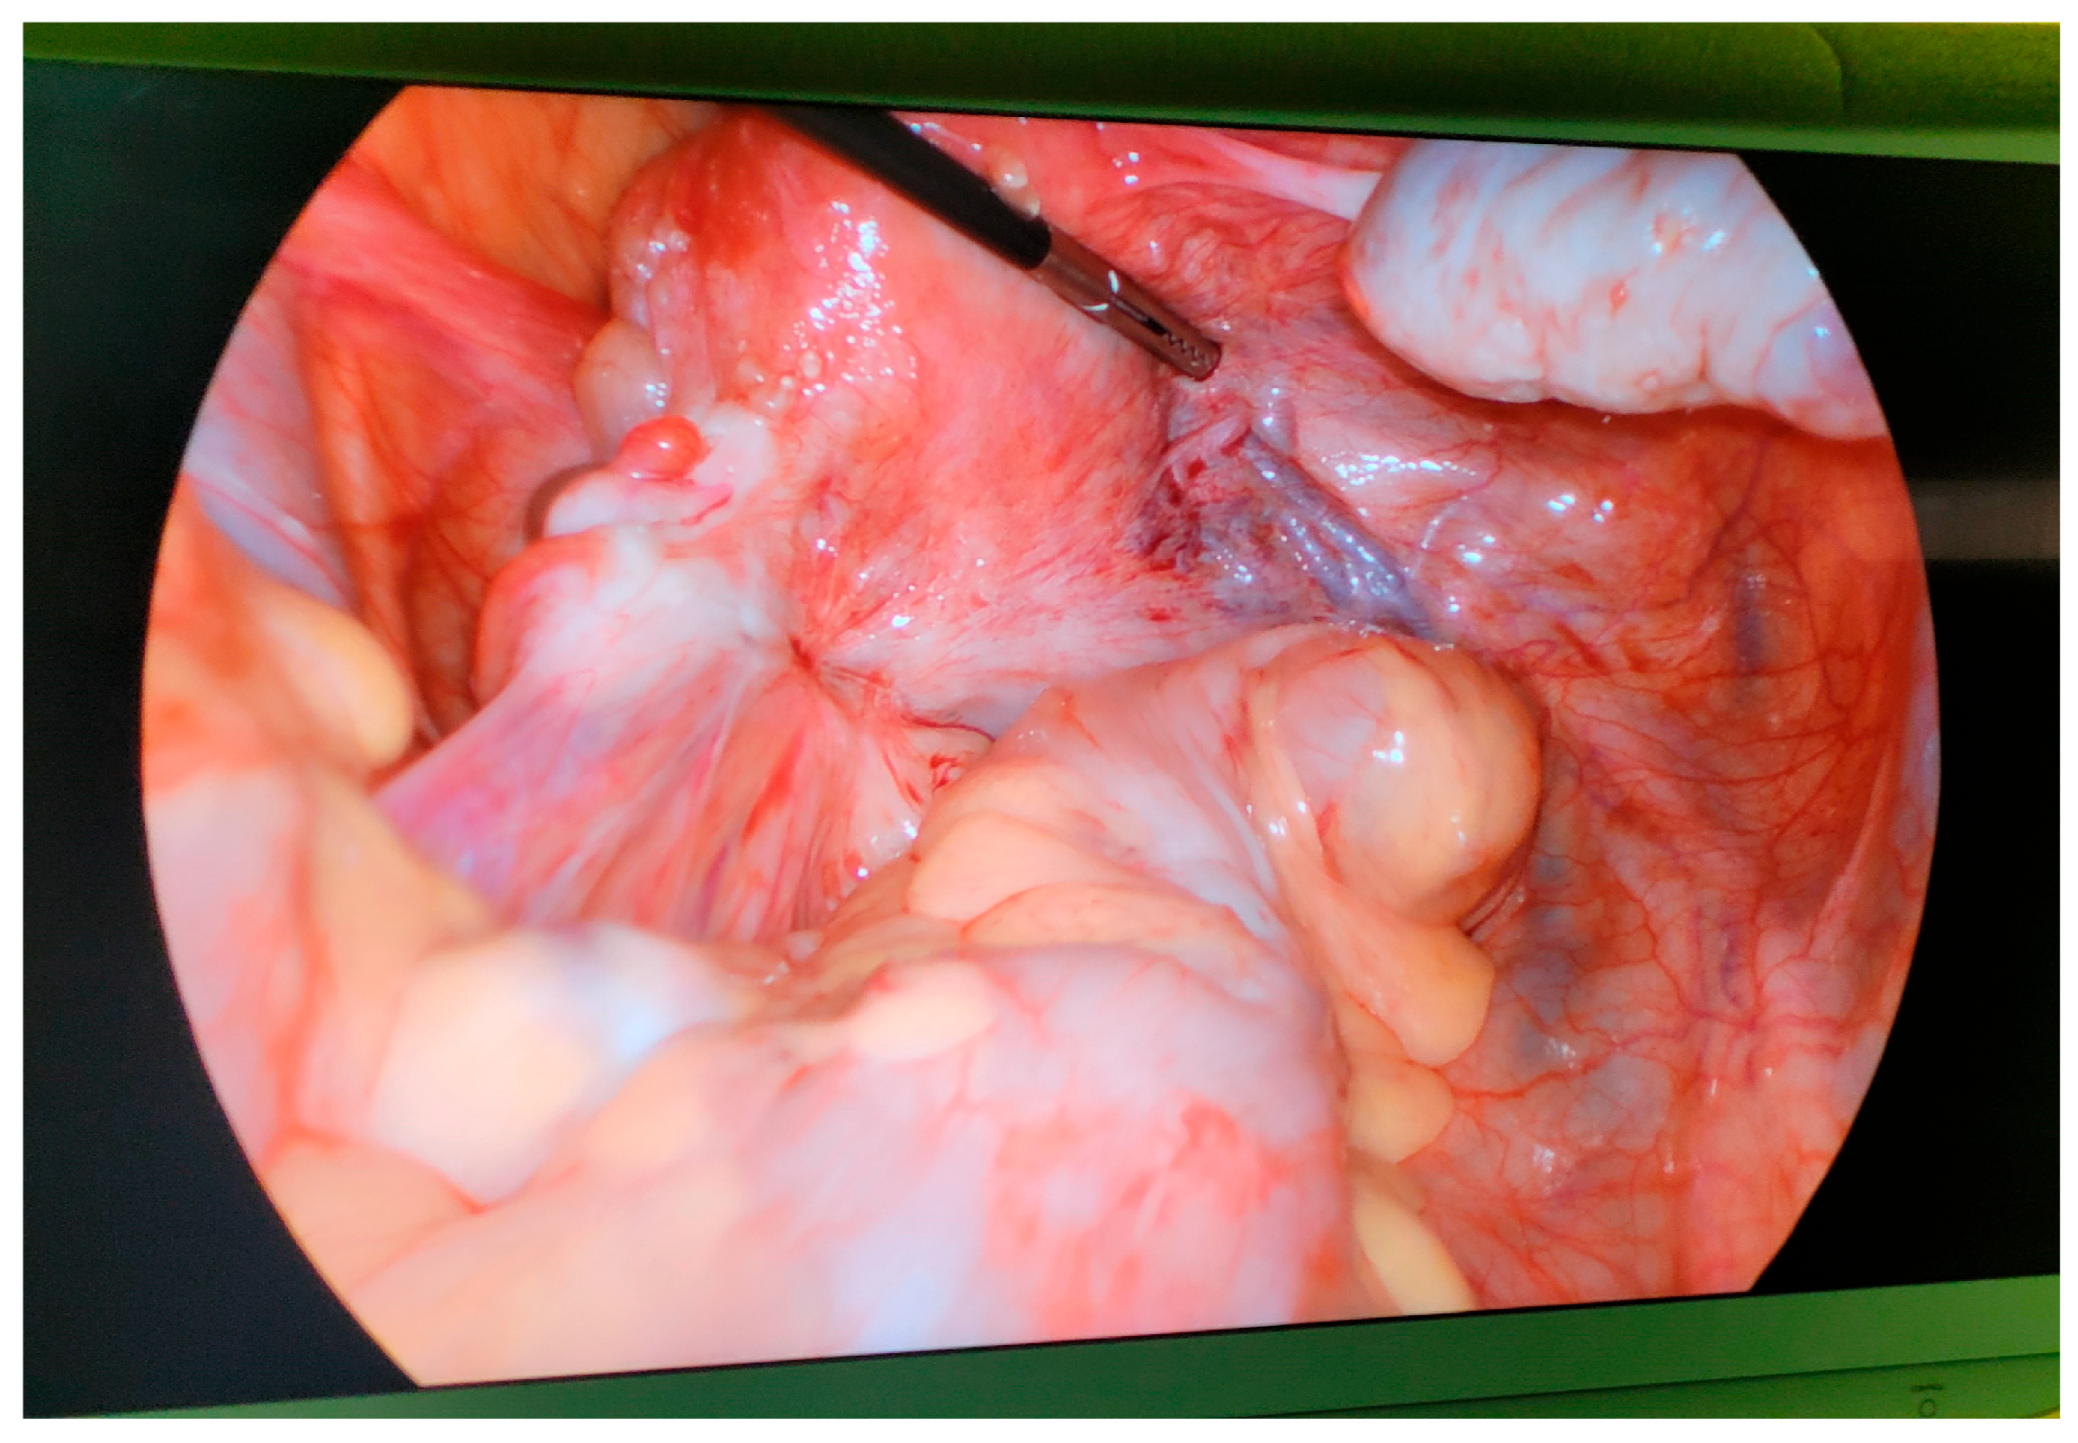

2.1. Pathophysiology and Classification